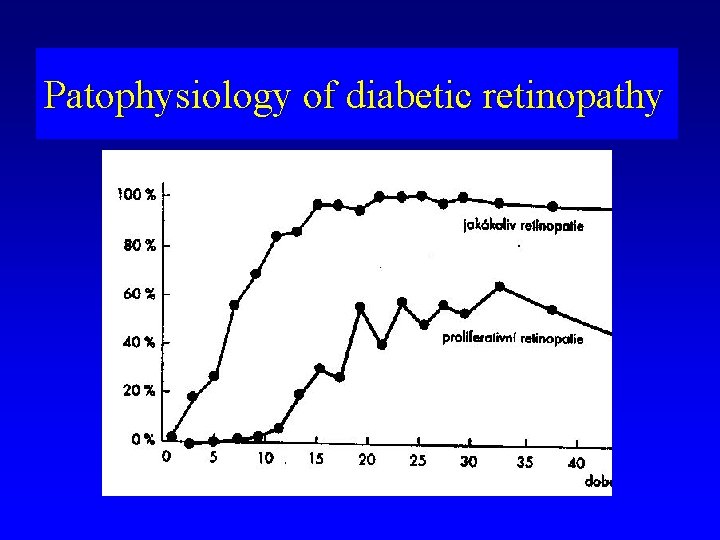

Diabetic retinopathy (epidemiology) • • • Diabetes mellitus- 8% population 25% diabetics - DR 5% diabetics - proliferative DR DR rare until first 3 -5 years of duration of DM DR in 60 - 90% after 15 - 20 years of duration of DM • DR in 97% after 30 years of duration of DM

Patophysiology of diabetic retinopathy